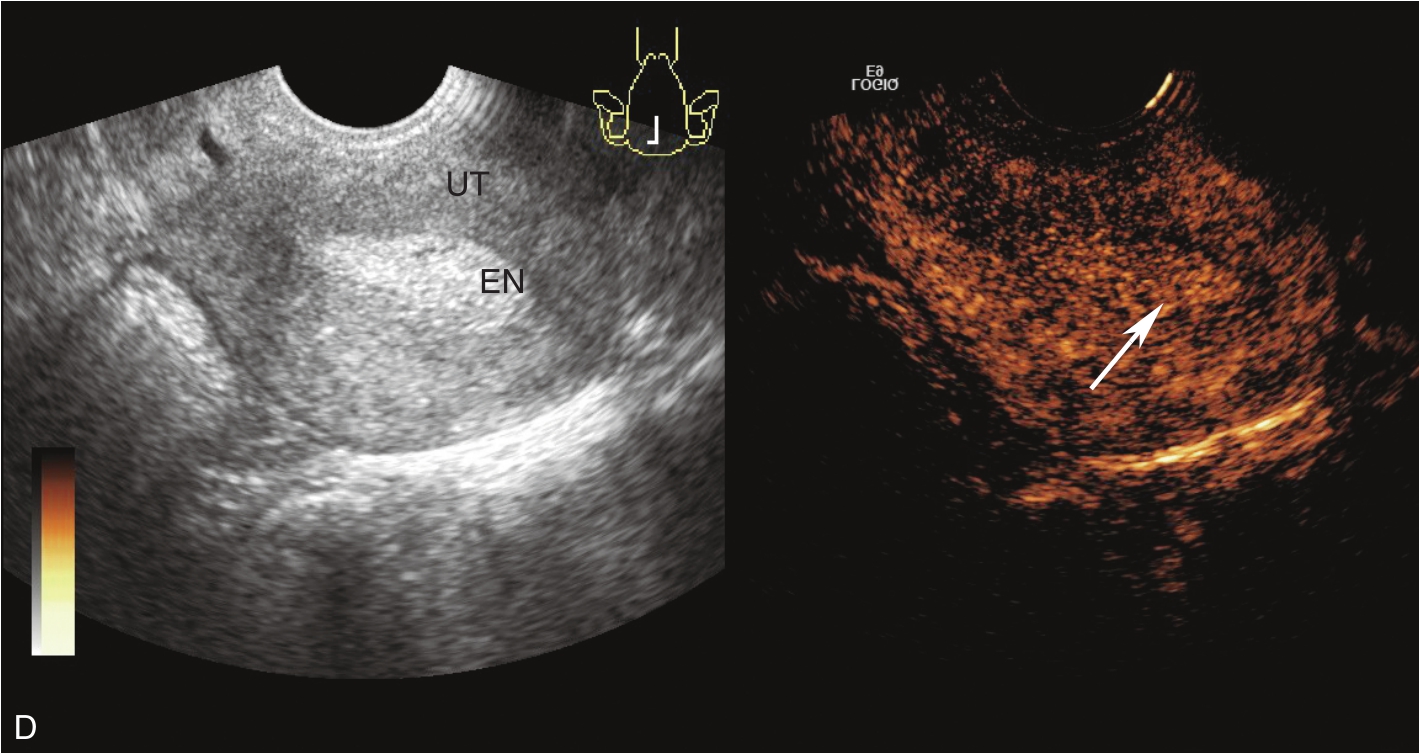

经阴道超声检查见图3-5-1。子宫后位,宫体大小约5.8cm×5.0cm×5.1cm,宫内膜厚约0.75cm(单层),内膜回声不均匀。宫腔未见分离。宫壁回声均匀。内膜内见多个囊性结节,较大者大小约0.5cm,内透声可。CDFI:未见异常血流信号。双侧附件区未见异常回声。盆腹腔未见明显积液。超声检查结果:宫内膜增厚伴回声不均匀。

图3-5-1 常规超声声像图

A.后位子宫的矢状切面(经阴道),子宫内膜增厚,单层厚约0.75cm,内见多个小暗区;B.后位子宫的横断面(经阴道);C.后位子宫的矢状切面(经阴道),彩色多普勒能量图超声检查显示子宫未探及明显血流信号;D.右卵巢;E.左卵巢。UT:子宫;EN:子宫内膜;R-OV:右卵巢;L-OV:左卵巢。